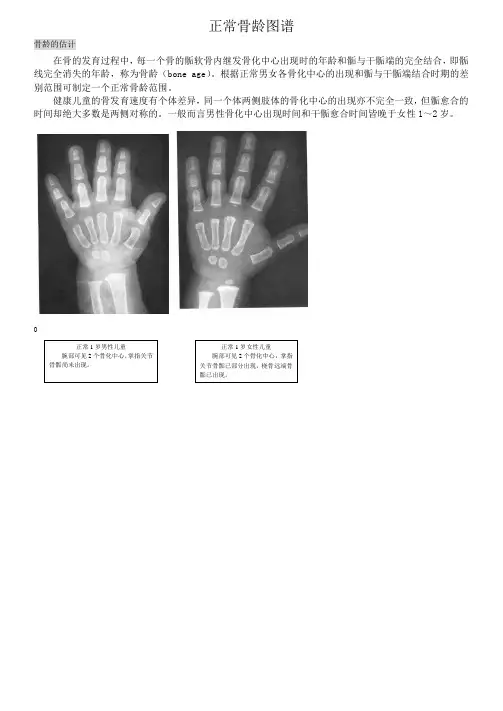

正常骨龄图谱

骨龄的估计

在骨的发育过程中,每一个骨的骺软骨内继发骨化中心出现时的年龄和骺与干骺端的完全结合,即骺线完全消失的年龄,称为骨龄(bone age)。

根据正常男女各骨化中心的出现和骺与干骺端结合时期的差别范围可制定一个正常骨龄范围。

健康儿童的骨发育速度有个体差异,同一个体两侧肢体的骨化中心的出现亦不完全一致,但骺愈合的时间却绝大多数是两侧对称的。

一般而言男性骨化中心出现时间和干骺愈合时间皆晚于女性1~2岁。